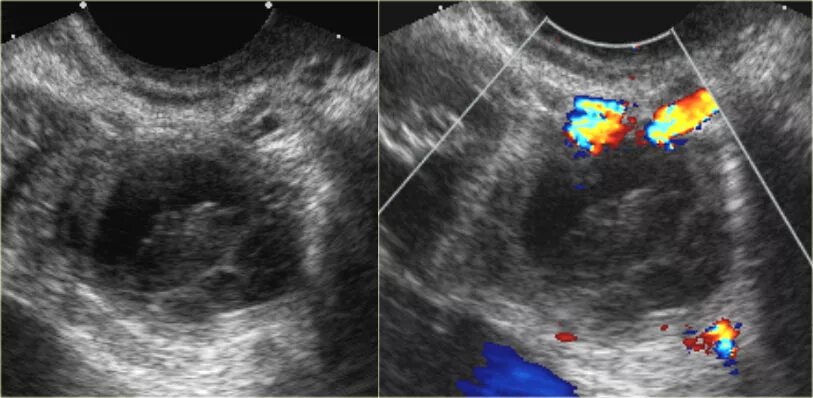

Как выглядит яичник